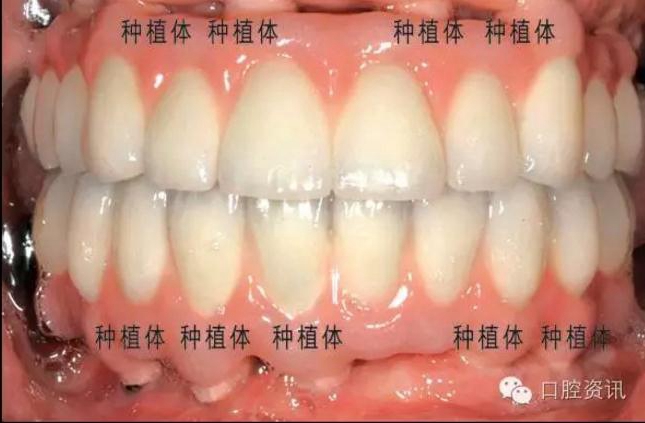

8. 種植牙和真牙看上去一模一樣嗎?

種植牙義齒可以代替單顆牙齒、連續(xù)多顆牙齒或者整排牙齒。正確的

植入和修復(fù)會使種植牙呈現(xiàn)令人滿意的美觀效果。目前, 先進(jìn)的臨床

技術(shù)和材料已經(jīng)可以讓種植牙修復(fù)達(dá)到令人滿意的美學(xué)效果。一般情

況下,是看不出來種植牙和真牙的區(qū)別的,真假難辨。

圖18. 種植牙修復(fù)上下頜全口牙缺失